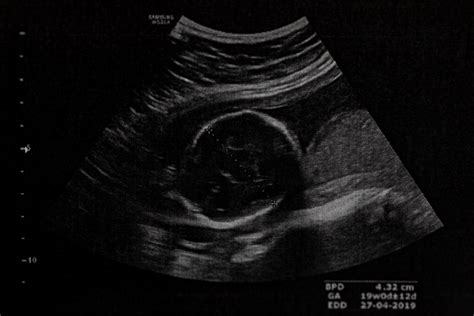

Niektoré ženy sa obávajú príliš skorého vyšetrenia. V prvých týždňoch tehotenstva, najmä v štvrtom týždni, nemusí byť na ultrazvuku vidieť viac ako gestačný vak. Srdiečko plodu je zvyčajne viditeľné okolo 7. až 8. týždňa tehotenstva. Preto niektorí lekári objednávajú prvé prehliadky až v tomto období, aby bolo možné vidieť akciu srdca a vylúčiť prípadné komplikácie.

Napríklad, niektoré mamičky uvádzajú, že po pozitívnom teste išli k lekárovi hneď, ale na ultrazvuku bol viditeľný len vak. Následne boli objednané o týždeň či dva, kedy už bolo vidieť srdiečko. V niektorých prípadoch lekár potvrdí tehotenstvo a vylúči mimomaternicové tehotenstvo, aj keď srdiečko ešte nie je viditeľné.